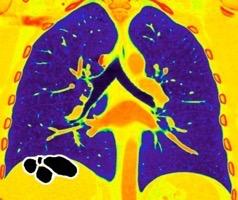

< Volumen pulmonar

Síndrome antisintetasa

(Miositis anti Jo-1).

Artralgias migratorias, Miositis, “Manos de mecánico”, Raynaud y Enfermedad

intersticial pulmonar (>70%).

Waseda Y et al.. Eur J Radiol. 2016